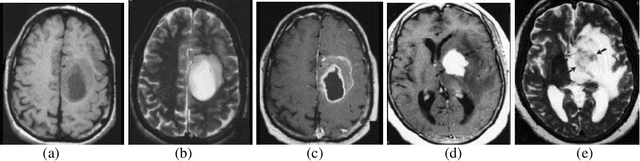

Abstract:Tumor segmentation from magnetic resonance imaging (MRI) data is an important but time consuming manual task performed by medical experts. Automating this process is a challenging task because of the high diversity in the appearance of tumor tissues among different patients and in many cases similarity with the normal tissues. MRI is an advanced medical imaging technique providing rich information about the human soft-tissue anatomy. There are different brain tumor detection and segmentation methods to detect and segment a brain tumor from MRI images. These detection and segmentation approaches are reviewed with an importance placed on enlightening the advantages and drawbacks of these methods for brain tumor detection and segmentation. The use of MRI image detection and segmentation in different procedures are also described. Here a brief review of different segmentation for detection of brain tumor from MRI of brain has been discussed.